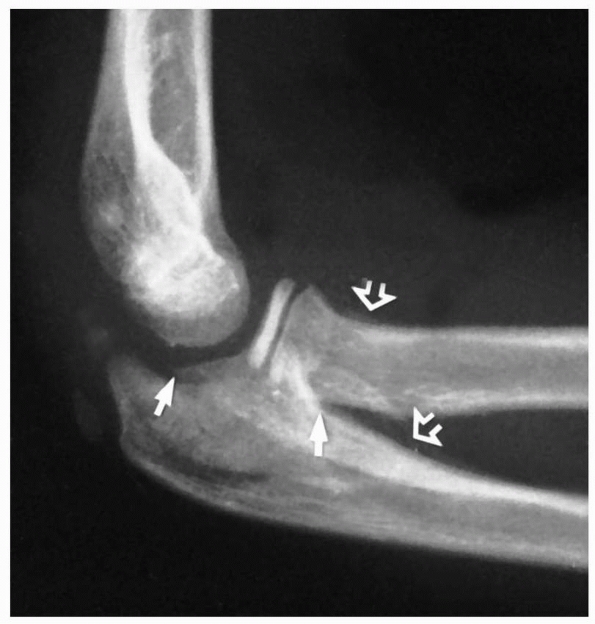

fracture of the radial neck may be difficult in children whose radial

head remains unossified. The only clue may be a little irregularity in

the smoothness of the proximal metaphyseal margin (Fig. 11-3). Rokito et al.93

FIGURE 11-3

Preosseous fracture. The only clue to the presence of a fracture of the radial neck with displacement of the radial head was loss of smoothness of the metaphyseal margin (arrow). |